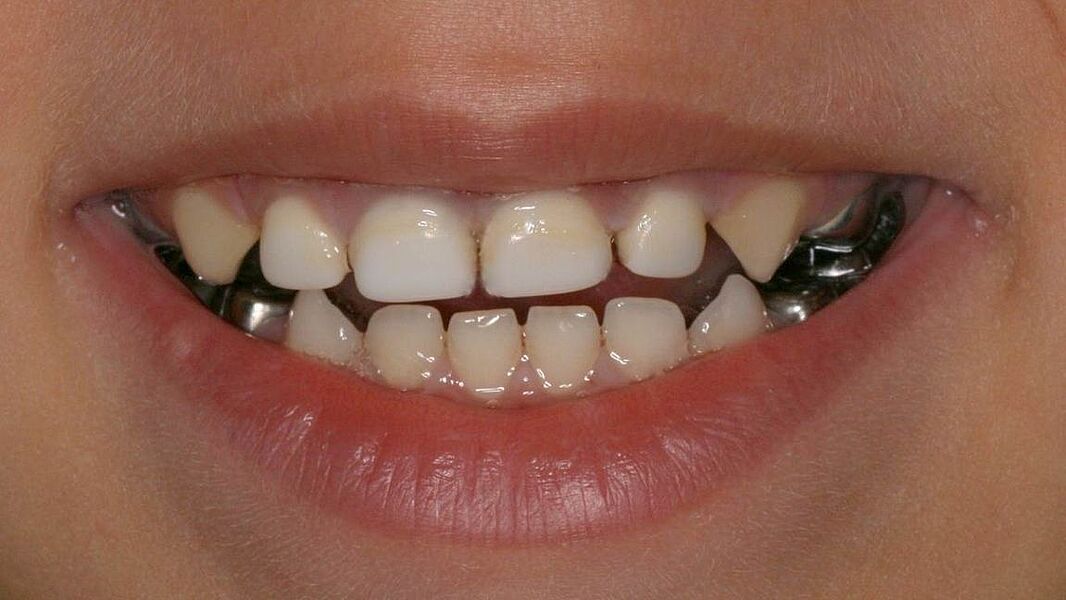

Dieses Milchgebiss wurde fachgerecht saniert. Die Karies ist verschwunden. Die Milchzähne werden erhalten, bis sie von den bleibenden Zähnen ersetzt werden. Dafür wurden auch Milchzahnkronen eingesetzt. Jetzt sind beste Bedingungen für eine effiziente Prophylaxe gegeben.